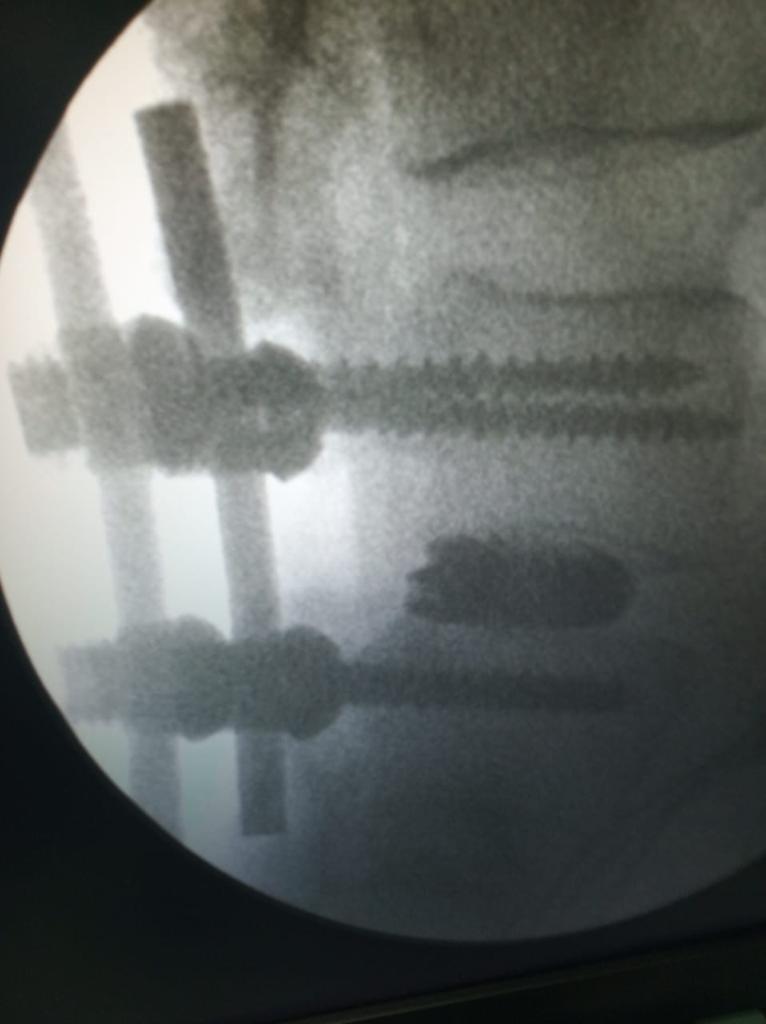

Cases